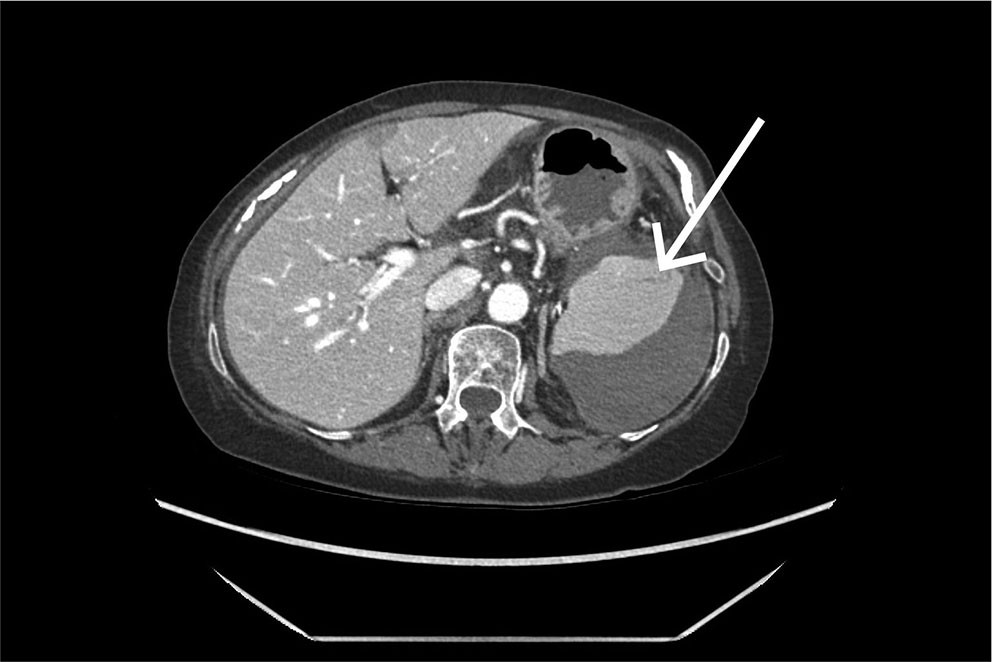

An urgent CT scan of the abdomen and pelvis with intravenous contrast in the portal venous phase was performed. The examination revealed a large subcapsular splenic haematoma and a small splenic laceration (Figure 1). It was concluded that a capsular rupture had likely occurred, with bleeding into the free abdominal cavity and fluid accumulation around the liver, colon and pelvis. Upon re-examination of the CT scan taken immediately after the colonoscopy, a small subcapsular splenic laceration was visible near the attachment of the splenocolic ligament (Figure 2).